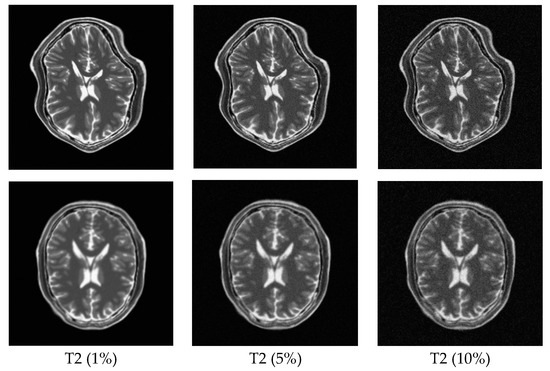

3.2.1. Test on the BrainWeb Dataset